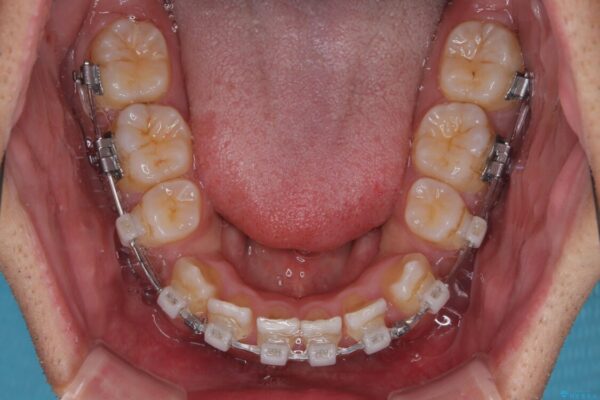

治療途中

• 八重歯と前歯のガタガタを抜歯矯正で治療|クリアブラケット使用例 治療途中画像

矯正装置は、審美性と費用面のバランスを考慮して、プラスチックブラケットとメタルワイヤーを使用しました。

透明感のあるブラケットを用いたため、従来の金属装置よりも目立ちにくく、日常生活での見た目の不安も軽減できます。